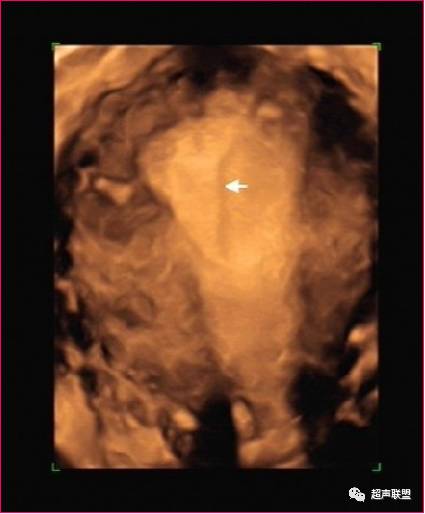

三维超声成像技术可获取二维超声不能得到的冠状面的回声信息,可以直接反映子宫外形和宫腔形态,形象完整地显示IUD的整体,清晰显示IUD有无断裂及嵌顿程度、部位。

同时,因计算机扫描的标准化、程序化,在重建回放检查过程中不易遗漏细节问题,如细碎的IUD残留及与宫壁的关系,从而为临床有的放矢地选择治疗措施提供可靠依据。

成像前的二维图像尽量完整地显示整个宫腔和宫颈管,以便成像后能比较容易地找出宫腔与IUD关系的清晰图像。

尽可能在患者月经周期的中后期进行检查,子宫内膜相对较厚,此时成像宫腔形态显示满意。

诊断: 宫内节育器位置下移

诊断宫内节育环部分嵌入

肌层可能,宫腔镜证实